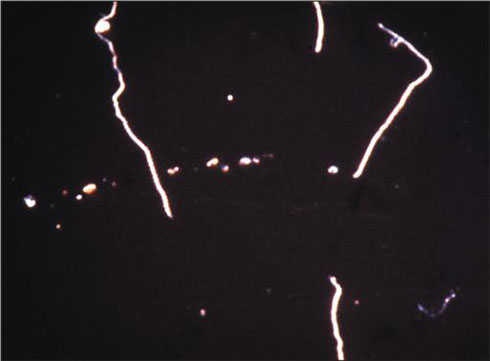

لپتوسپیراها، اسپیروكتهای گرم منفی هوازی هستند كه 6 تا12 میكرومتر طول و 0/1 میكرومتر قطر دارند و در دو انتها دارای قلاب بوده و یك فیلامانت محوری دارند (شكل 1). این باكتری را به آسانی بوسیله حركت چرخشی یا مارپیچیاش و قلاب مشخصی كه در یك یا هر دو انتهای آن است میتوان تشخیص داد. باكتریهای لپتوسپیرا بدلیل حركات شدید و ضخامت كمشان قادرند از صافیهای با اندازه ریز 0/22 تا 0/45 میكرومتر كه اغلب باكتریها از آنها رد نمیشوند، رد شوند. لپتوسپیرا کاتالاز و اکسیداز مثبت است و از اسیدهای چرب با زنجیره بلند به عنوان منبع انرژی و کربن استفاده میکند. نمکهای آمونیم مهمترین منبع نیتروژن است. در pH قلیایی زنده بوده و آنها به 8 آزو گوانین حساس میباشند.

جنس لپتوسپیرا شامل دو گونه است : 1)لپتوسپیرا اینتروگانس(Leptospira interrogans) (بیماریزا)، 2) لپتوسپیرا بیفلكسا (غیر بیماریزا). گونه پاتوژنیك لپتوسپیرا اینتروگانس دارای سروگروپ یا سرووارهای (تیپهای سرولوژیك) متعددی میباشند (230 سروواریته). این سرووارها را براساس میزبانی كه آلوده میكنند، تقسیم مینمایند. مثلاً میزبان سرووار ایكترهموراژیه (Icterohaemorrhagiae ) راتها هستند، درحالیكه میزبان سرووار پومونا (Pomona) و كانیكولا (Canicola) به ترتیب سگ و خوكها هستند. بیماری از این میزبانها به انسان منتقل میشود و حیوانات مخزن باكتری محسوب میشوند. از لحاظ شكل ظاهری گونههای بیماریزا و ساپروفیتهای (غیربیماریزا) لپتوسپیرا از یكدیگر قابل تفكیك نیستند و بهترین وسیله برای مشاهده این اجرام، استفاده از میكروسكوپ زمینه تاریك است.

شكل 1: تصویر میكروسكوپ زمینه تاریك لپتوسپیرا اینتروگانس.

خون، مایع نخاع و ادرار را ابتدا برای جداسازی عناصر سلولی و بعد در دور بالا برای جداسازی باكتری سانتریفوژ كرده و سپس از رسوب گسترش تهیه نموده و پس از رنگآمیزی فونتانا با میكروسكوپ نوری و یا تهیه Wet mountتوسط میكروسكوپ زمینه سیاه به مشاهده باكتری میپردازند. از لحاظ شكل ظاهری گونههای بیماریزا و ساپروفیتها (غیربیماریزا) لپتوسپیرا از یكدیگر قابل تفكیك نیستند و بهترین وسیله برای مشاهده این اجرام، استفاده از میكروسكوپ زمینه تاریك است. لپتوسپیرا با رنگهای آنیلینی بخوبی رنگآمیزی نمیشوند.